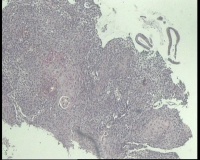

请老师 看看,宫颈活检,宫颈CINIII累腺局灶早期浸润还是直接报宫颈鳞癌?

鳞状上皮全层异型增生,局灶基底膜不清,请老师看看巢状分布的是累腺还是浸润?

CIN3累腺,不排除有浸润的可能。

有浸润,鳞癌